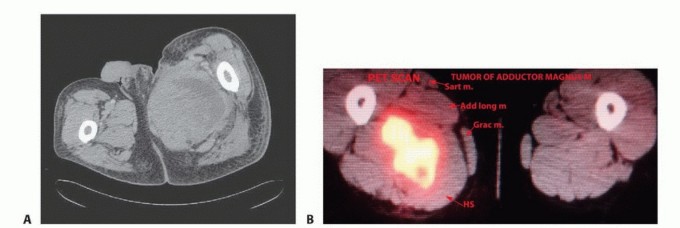

لطالما شكلت أورام الأنسجة الرخوة في الفخذ تحديًا كبيرًا للأطباء والمرضى على حد سواء، خاصة تلك التي تنمو في منطقة العضلات المقربة الحساسة. هذه المنطقة، التي تقع في الجزء الداخلي من الفخذ، هي ثاني أكثر المواقع شيوعًا لظهور هذه الأورام بعد الجزء الأمامي، وتتسم بقربها الشديد من الحزمة العصبية الوعائية الرئيسية (الشريان الفخذي، الوريد الفخذي، العصب الفخذي)، مما يجعل أي تدخل جراحي فيها محفوفًا بالمخاطر ويتطلب دقة متناهية وخبرة جراحية استثنائية.

ما يجعل هذه المنطقة صعبة ومعقدة جراحيًا هو قربها الشديد من الهياكل التشريحية الحيوية:

- الحزمة العصبية الوعائية الفخذية (Femoral Neurovascular Bundle): يمر الشريان الفخذي والوريد الفخذي والعصب الفخذي (الذي يعصب الجزء الأمامي من الفخذ) بالقرب من هذه العضلات، مما يجعل استئصال الأورام في هذه المنطقة يتطلب دقة فائقة لتجنب إصابة هذه الأوعية والأعصاب الحيوية.

- العصب الوركي (Sciatic Nerve): يمر أيضًا بالقرب من الجزء الخلفي من مجموعة العضلات المقربة، خاصة العضلة المقربة الكبيرة، مما يزيد من تعقيد الجراحة.